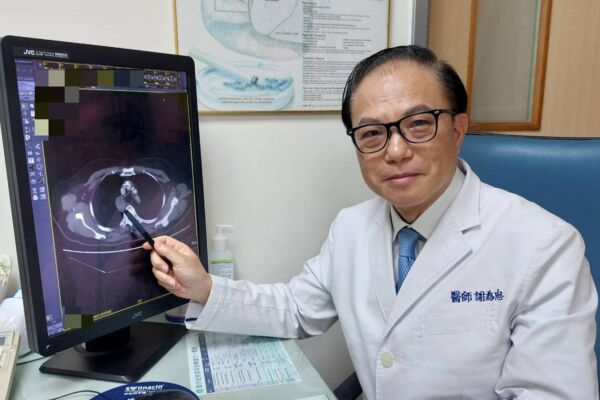

大千綜合醫院醫療副院長暨胸腔內科醫師謝為忠表示,過去面對病人在第一線治療出現抗藥性時,只能嘗試新藥物或是沒使用過的其他藥物,卻會有費用昂貴且效果不明的缺點,對病人及家屬都是很大的負擔。現今,透過抽血或取腫瘤組織做次世代定序基因檢測(NGS),可判斷出病人癌細胞的突變基因,協助醫師擬定適合的治療策略,精準選擇用藥,並針對副作用調整劑量,進而達到更好的治療效果,讓每位病人獲得最適切的個人化治療。

謝為忠醫療副院長強調,雖然次世代定序基因檢測(NGS)在去年5月通過健保給付,但對於此項檢測的醫院資格要求相當嚴格,非醫學中心的醫院只有少數通過審核。今年2月大千綜合醫院順利通過衛福部審核,成為苗栗縣唯一通過癌症品質認證及執行次世代定序基因檢測的醫院,期望透過醫療團隊的努力,可以為苗栗縣的癌症診斷及治療的醫療服務。◇